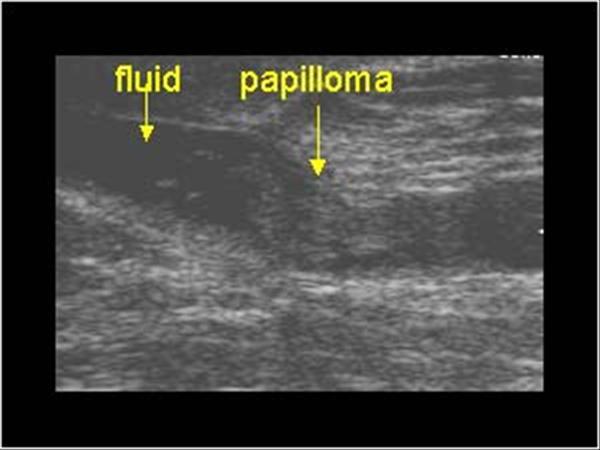

complex cyst vs intraductal papilloma

What is Intraductal Papilloma?

benign breast condition

Benign tumor originating from the ductal epithelium and projecting into the lumen of the duct. Commonly in women ages 35 to 55.

What is the Sonographic Appearance of Intraductal Papilloma?

Less than 2 mm

Subareolar region

broad-based

pedunculated

fibrovascular stalk

What are the presentations of Intraductal Papilloma?

bloody discharge, feeling of fullness or pain in the areola